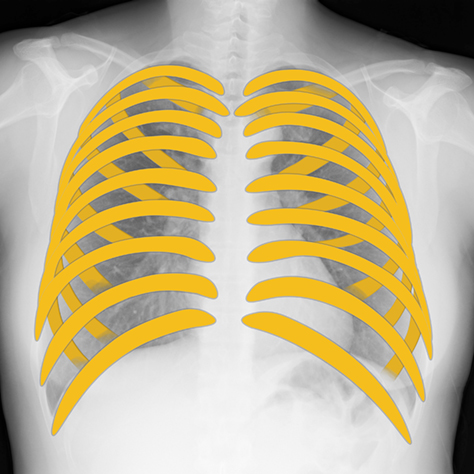

PLAMAX MF-72 minimum factory イングラム & クラブマン, Bone Suppression処理(胸部骨減弱処理) | コニカミノルタ,

Bone Suppression処理(胸部骨減弱処理) | コニカミノルタ, Bone Suppression処理(胸部骨減弱処理) | コニカミノルタ,

Bone Suppression処理(胸部骨減弱処理) | コニカミノルタ,S.H.MonsterArts ゴジラ(2016) 第4形態 夜間戦闘Ver.